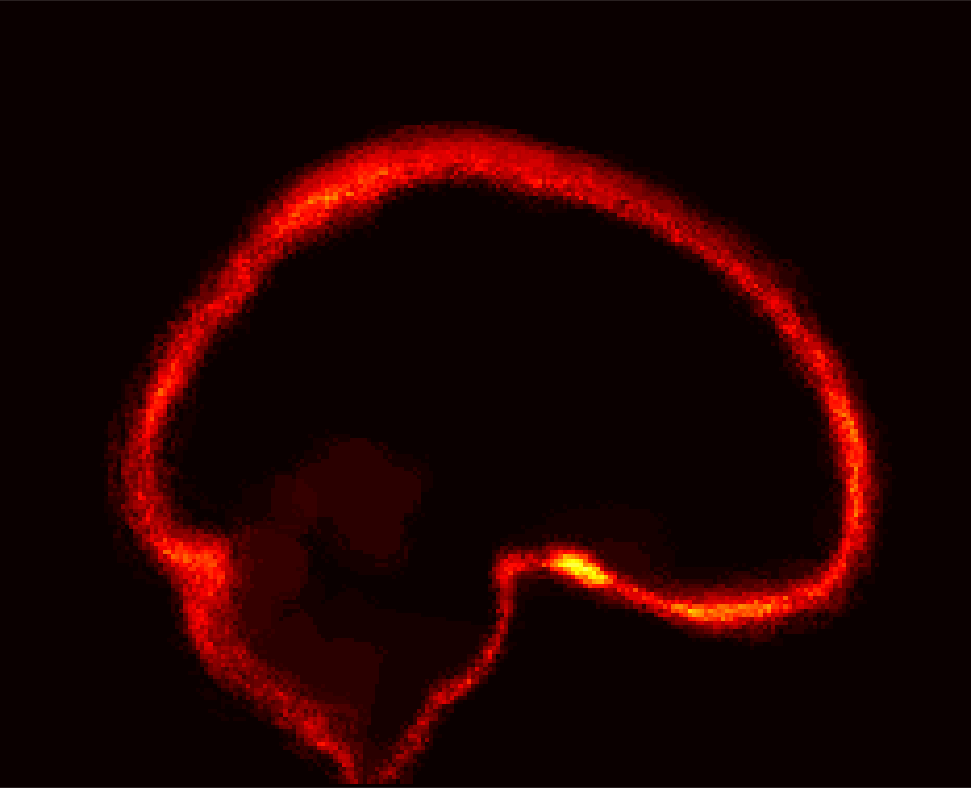

Fig. 1 shows example images from each dataset to illustrate image variability. IBSR and LPBA40 contain images from normal subjects and include large portions of the neck; BRATS has very low out-of-plane resolution; and the TBI dataset contains large pathologies and abnormal skulls.

Refer to caption

Figure 1: Illustration of image appearance variability on a selection of images from each (evaluation) database. From top to bottom: IBSR, LPBA40, BRATS and TBI.